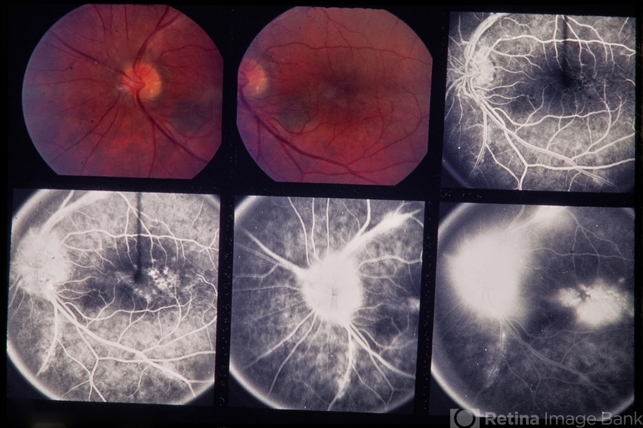

- PDR

- 35-year-old white male. 20/40 and 20/50. Proliferative diabetic retinopathy.